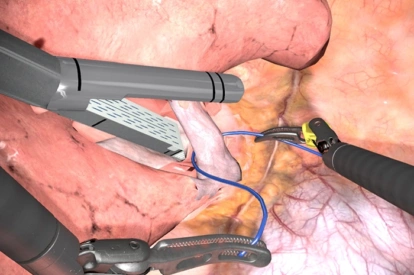

- Highly realistic graphics of human anatomy and simulation of tissue response to instruments

Stapler Module

- Complication management: simulation of errors and bleedings

- Tutorials: videos of experts performing tasks and procedures on the simulator along with videos of real procedures